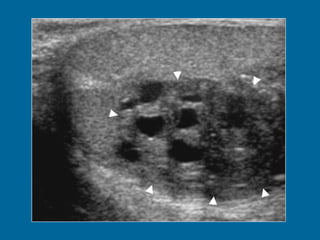

Intratesticular varicocele in a 38-year-old man.  (a) Transverse oblique US scan of left testis reveals multiple intratesticular anechoic cystic areas (arrowhead).  (b) Duplex Doppler US scan shows that venous flow in these cystic areas increases during a Valsalva maneuver (arrowhead).

Intratesticular varicocele ina 38-year-old man. (a) Transverse oblique US scan of left testis reveals multiple intratesticular anechoic cystic areas (arrowhead). (b) Duplex Doppler US scan shows that venous flow in these cystic areas increases during a Valsalva maneuver (arrowhead).